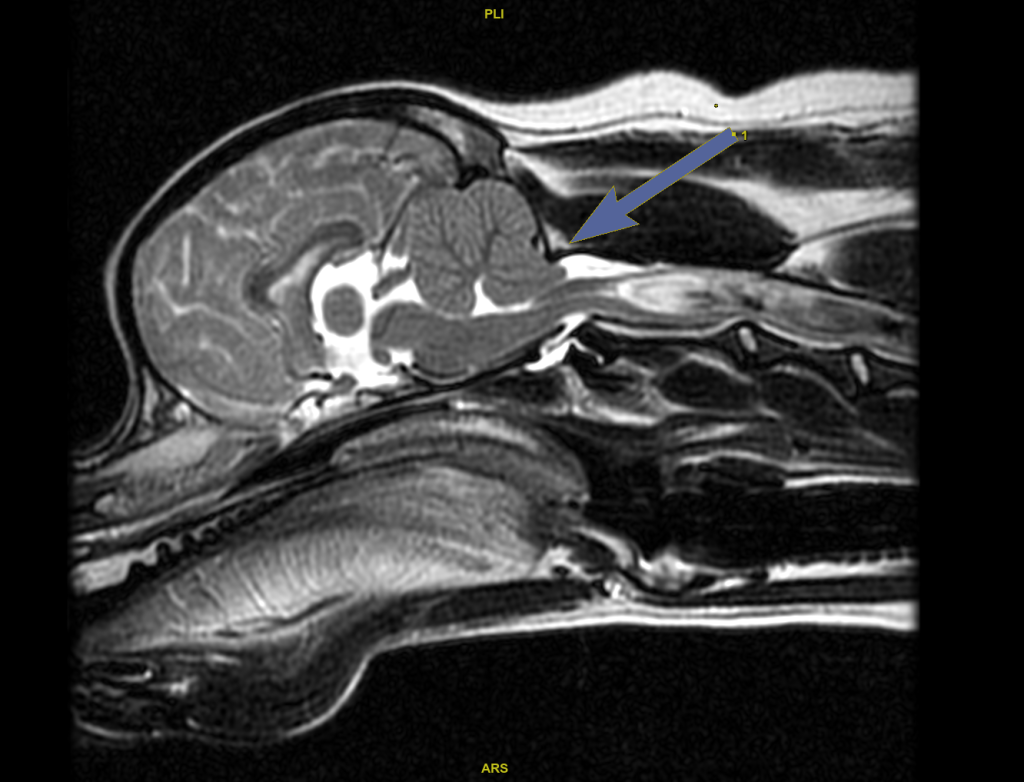

Leczenie malformacji Chiariego i jamistości rdzenia kręgowego

To specjalistyczny zabieg neurochirurgiczny stosowany w leczeniu chorób związanych z nieprawidłową budową doogonowej części czaszki. Najczęściej wykonywany jest u psów z malformacją Chiariego (Chiari-like malformation) oraz towarzyszącą jej jamistością rdzenia kręgowego (syringomyelia).

Schorzenia te prowadzą do zaburzeń przepływu płynu mózgowo-rdzeniowego i mogą powodować przewlekły ból oraz postępujące objawy neurologiczne.

Malformacja Chiariego polega na nieprawidłowej budowie tylnej części czaszki, która powoduje ucisk struktur mózgu oraz zaburzenia krążenia płynu mózgowo-rdzeniowego.

W konsekwencji może dojść do powstania jam w obrębie rdzenia kręgowego, czyli tzw. jamistości rdzenia kręgowego.

Podstawowym badaniem umożliwiającym rozpoznanie malformacji Chiariego oraz jamistości rdzenia kręgowego jest rezonans magnetyczny (MRI).

Badanie pozwala dokładnie ocenić:

Plastyka kości potylicznej polega na chirurgicznym powiększeniu przestrzeni w tylnej części czaszki poprzez usunięcie fragmentu kości potylicznej. Zabieg ten zmniejsza ucisk na struktury mózgu i poprawia przepływ płynu mózgowo-rdzeniowego.